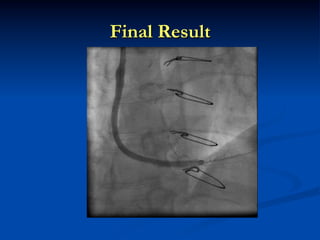

Final Result

After Aspiration SVG occlusion Manual Aspiration Injection through aspiration catheter

• 6.